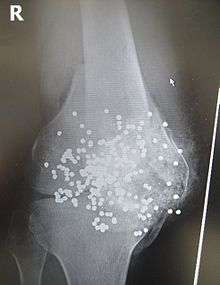

Persons with major trauma commonly have chest and pelvic X-rays taken,[6] and depending on the mechanism of injury and presentation a focused assessment with sonography for trauma (FAST) exam to check for internal bleeding. For those with relatively stable blood pressure, heart rate, and sufficient oxygenation, CT scans are useful.[6][24] Full-body CT scans, known as pan-scans, improve the survival rate of those who have suffered major trauma.[25][26] These scans use intravenous injections for the radiocontrast agent, but not oral administration.[27] There are concerns that intravenous contrast administration in trauma situations without confirming adequate renal function may cause damage to kidneys, but this does not appear to be a significant concern.[24]

In the U.S., CT or MRI scans are performed on 15% of those with trauma in emergency rooms.[28] Where blood pressure is low or the heart rate is increased—likely from bleeding in the abdomen—immediate surgery bypassing a CT scan is recommended.[29] Modern 64-slice CT scans are able to rule out with a high degree of accuracy significant injuries to the neck following blunt trauma.[30]